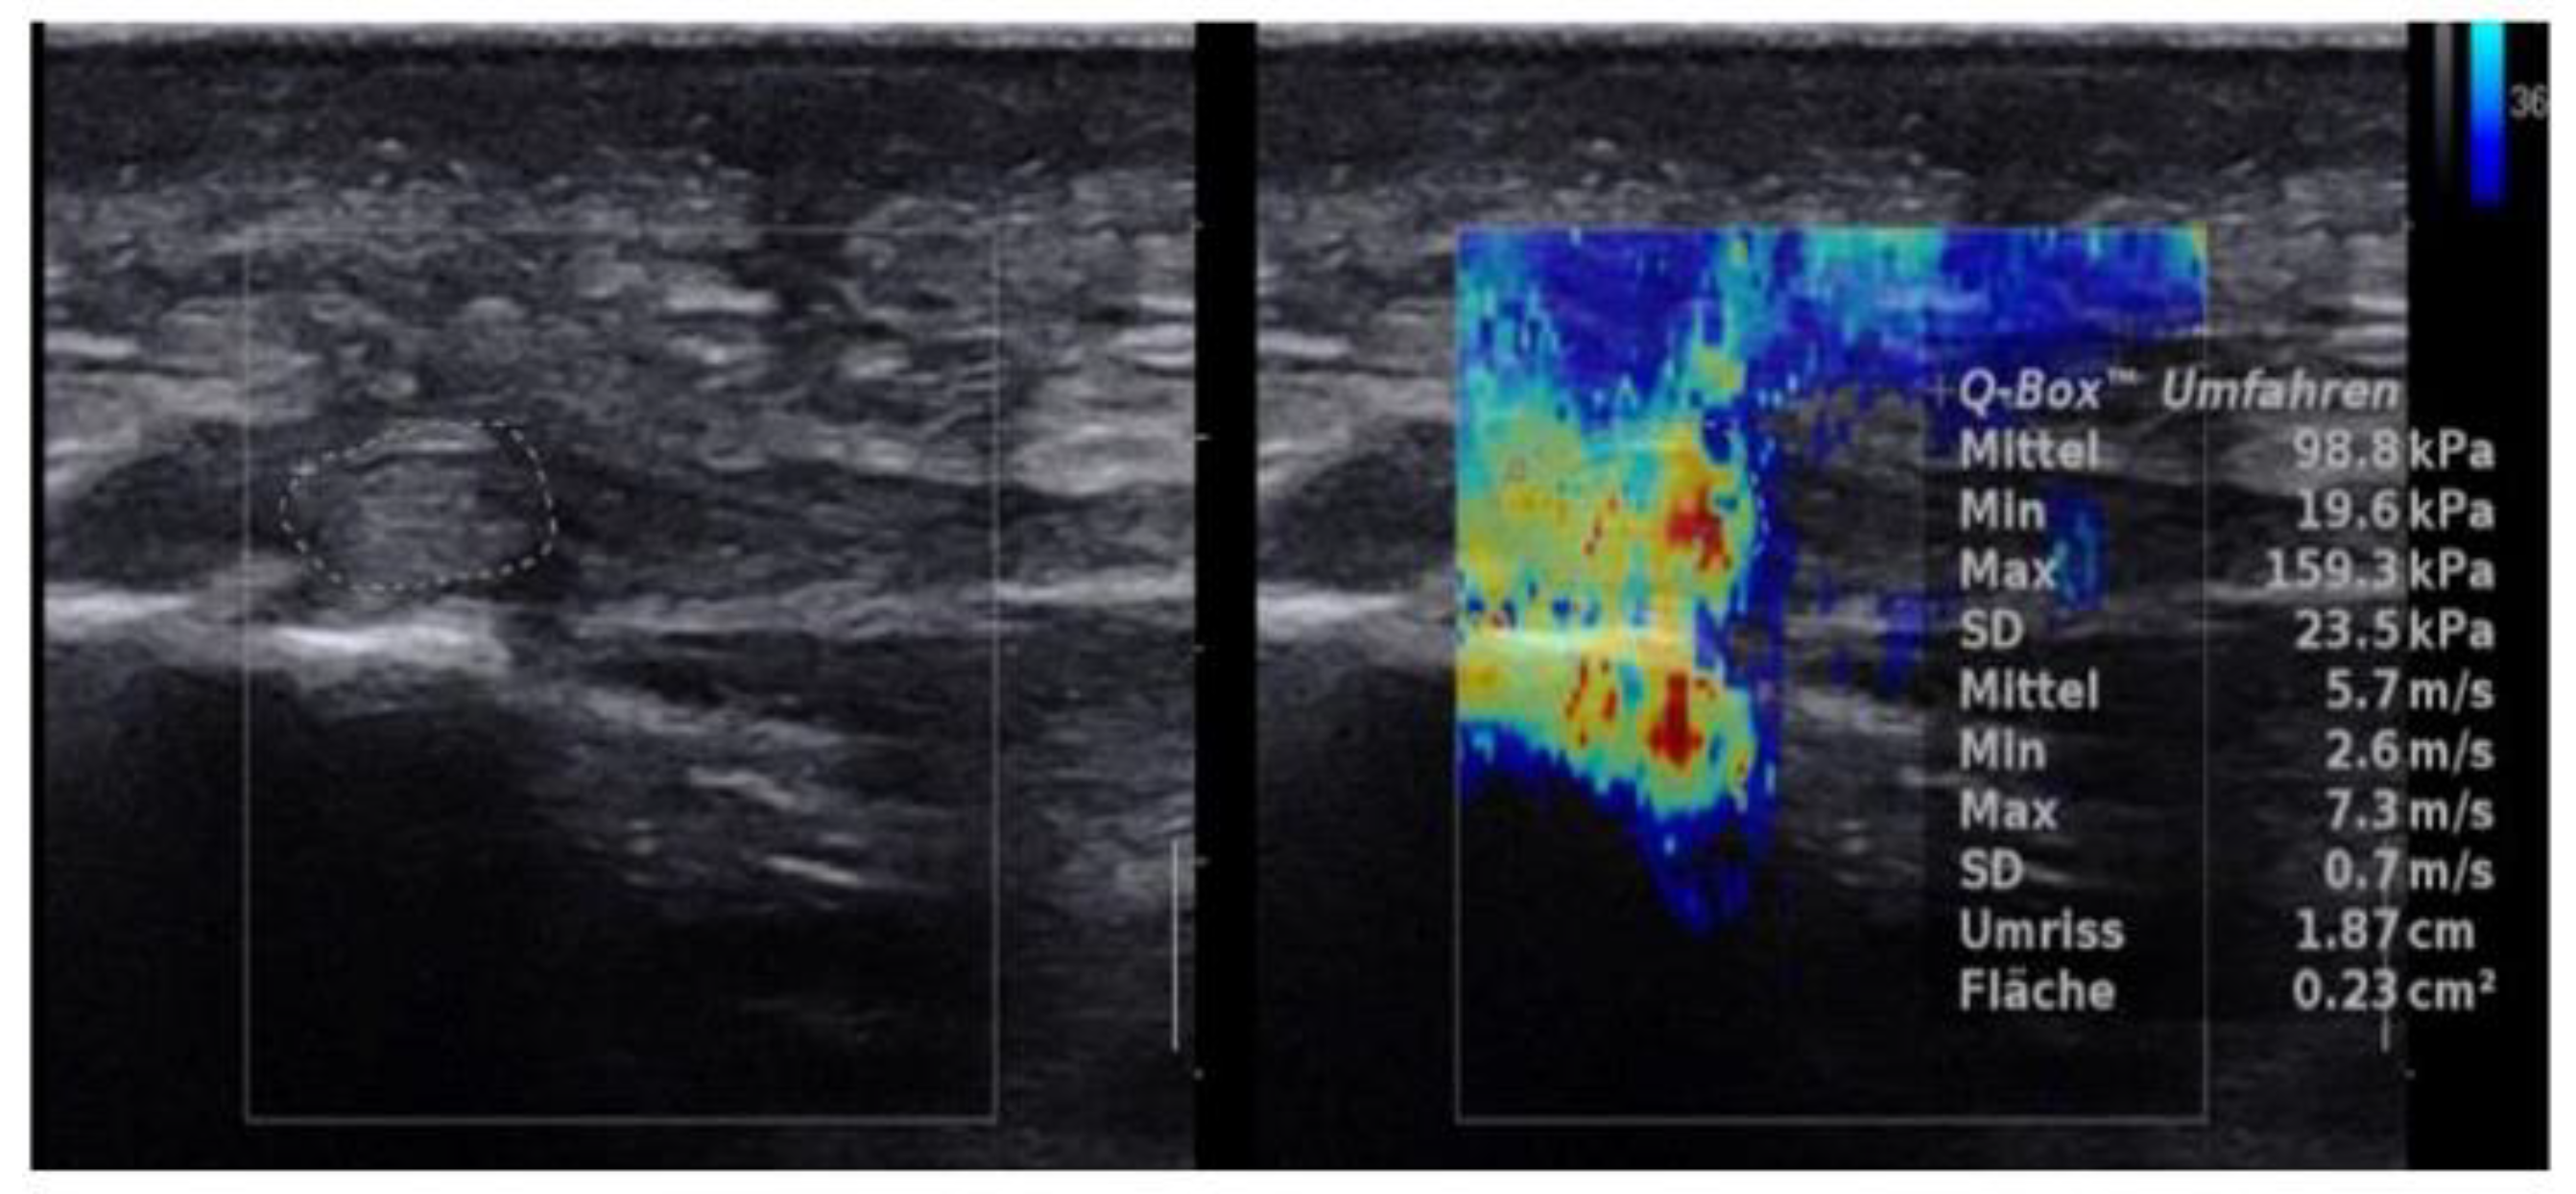

2.4.3. SWE Examination

3. Results